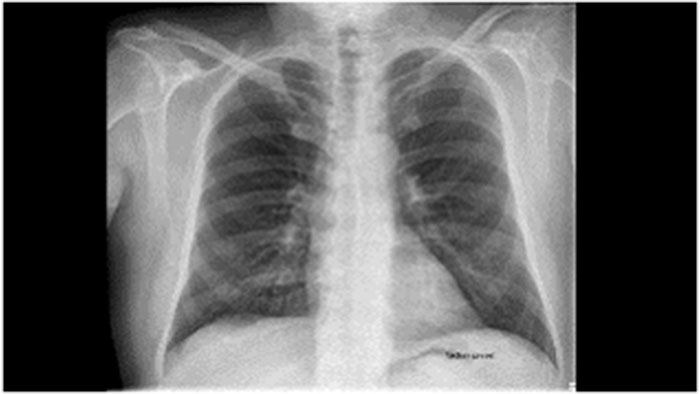

Kompleksowe narzędzie do przeglądania danych pozyskanych różnymi metodami obrazowania — w jednej przeglądarce

Lekarze często wymagają przeglądania obrazów rentgenowskich i fluoroskopowych pacjenta wraz z obrazami pozyskanymi metodą tomografii komputerowej, rezonansu magnetycznego, medycyny nuklearnej czy USG. W przypadku radiologów i lekarzy dokonujących przeglądu badań MR lub CT pacjenta konieczne może być także zapoznanie się z poprzednimi bądź ostatnimi badaniami RTG/fluoroskopowymi danej osoby w celu skutecznej oceny zmiany chorobowej lub progresji choroby. W związku z tym istotne jest zapewnienie radiologom możliwości korzystania z jednej platformy z rozwiązaniami do różnego rodzaju badań.

Uzyskiwanie całościowego obrazu stanu pacjenta rozpoczyna się od wyświetlenia i analizy obrazów pozyskanych różnymi metodami obrazowania w pojedynczym środowisku przeglądania. W takiej sytuacji przydatna okazuje się analiza ilościowa i ocena stadiów chorób z użyciem szeregu narzędzi do analizy danych 3D oraz informacji z takich badań obrazowych, jak badania CT, MR i wiele innych.